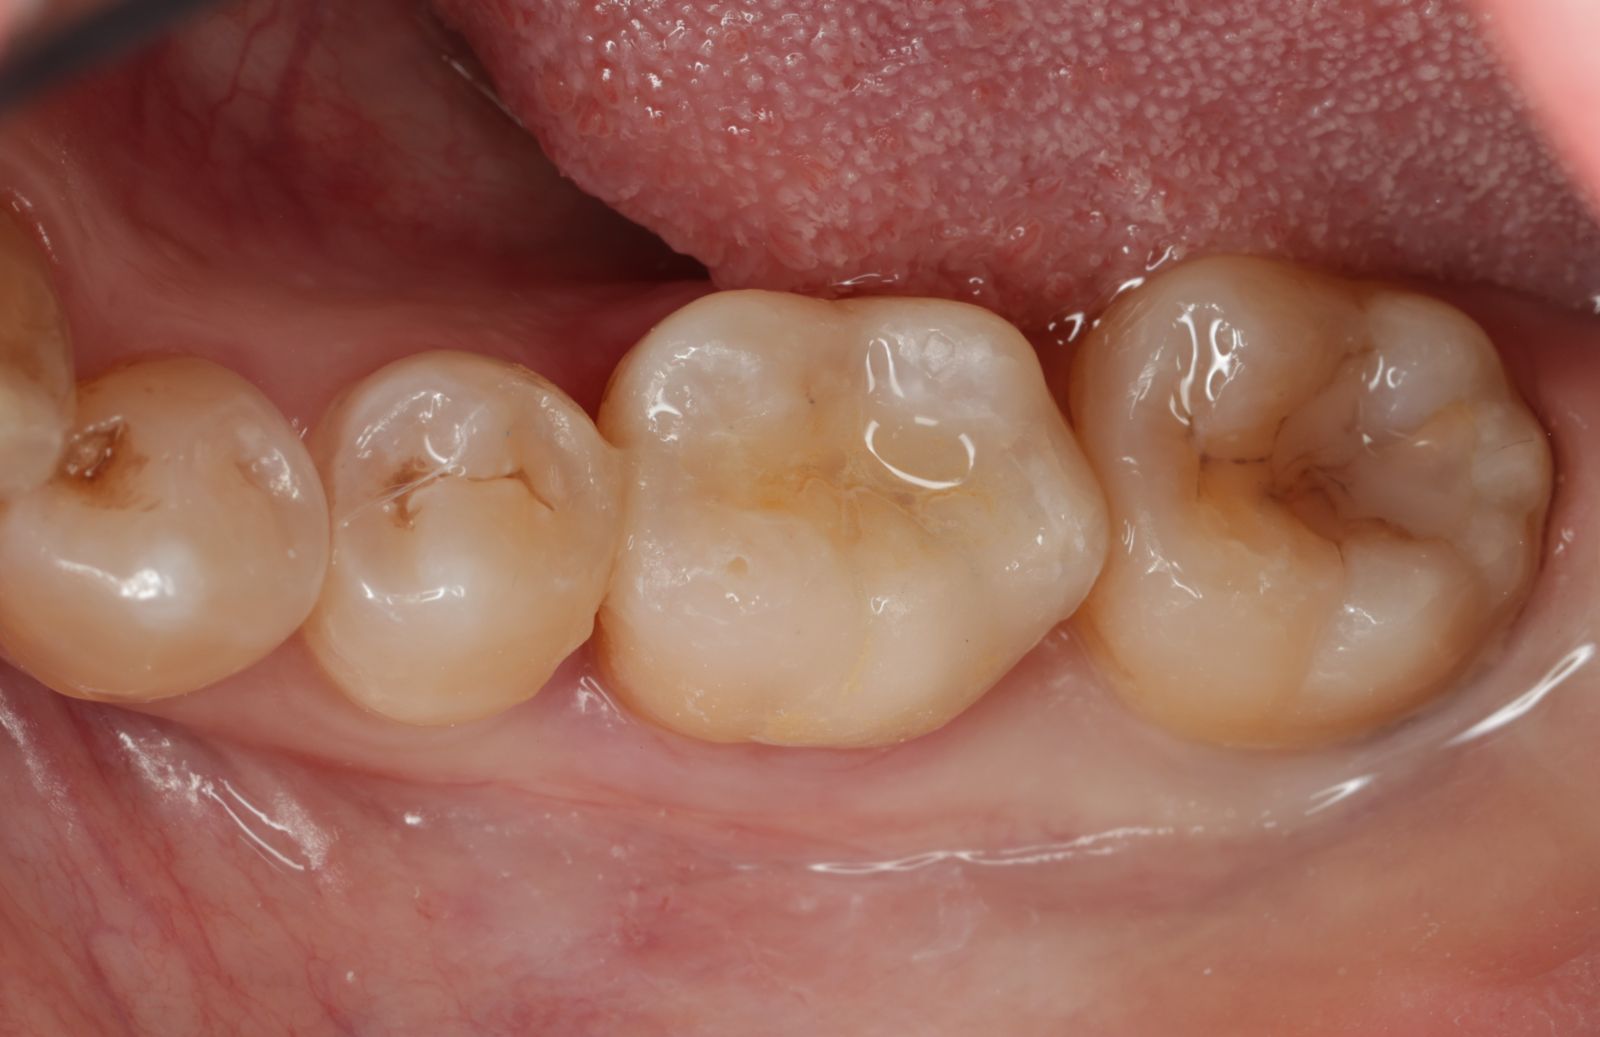

【 案 例 二 】